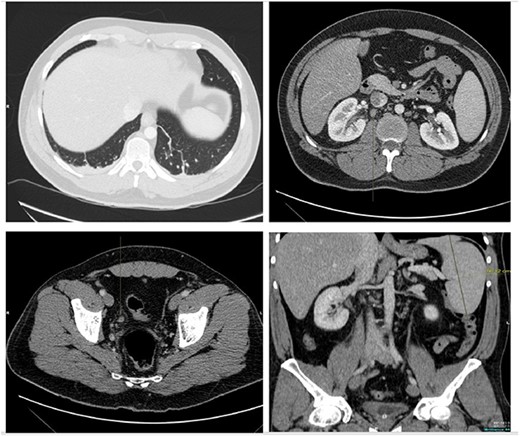

He presented with right sided abdominal pain associated with jaundice, fever, myalgia and arthralgia after receiving his second dose of the penultimate cycle of intra-renal BCG instillation. He did not have any tuberculosis contacts. His parameters on admission were stable. C-reactive protein levels were 230 mg/l and white cell count (WCC) was 6.51 × 109/l. His liver function tests were deranged, with a mixed obstructive and hepatitic picture. A CT kidneys, ureters and bladder (KUB) showed mild diffuse dilatation of the right ureter and renal pelvis with minimal amount of peri-ureteric fat stranding (Fig. 1). A CT scan of the abdomen with intravenous contrast (IV) was performed, this showed a distended right ureter down to the vesicoureteric junction, peri-ureteric fat stranding and lymphadenopathy in the aorto-caval space together with splenomegaly and atelectatic changes (Fig. 2).

A CT scan of the abdomen with IV contrast showed atelactic changes in the lung bases (top left), reactive hilar nodes (top right), a distended right ureter all the way down to the vesicoureteric junction surrounded by fat stranding (bottom left) and splenomegaly (bottom right).